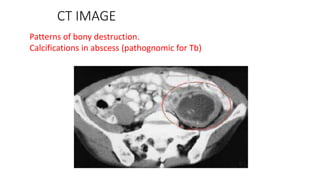

CT IMAGE

Patterns of bony destruction.

Calcifications in abscess (pathognomic for Tb)

CT IMAGE Patterns ofbony destruction. Calcifications in abscess (pathognomic for Tb)